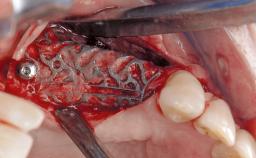

Surgical Management of Peri-Implantitis: Removal of Implant Due to Recurrent Infection Using an Implant-Retrieval Tool

Despite anti-infective surgical treatment, some patients may experience recurrent infection and progressive bone loss requiring additional treatment. This case describes a conservative approach using an implant retrieval tool without the need for excessive bone removal or use of a trephine.